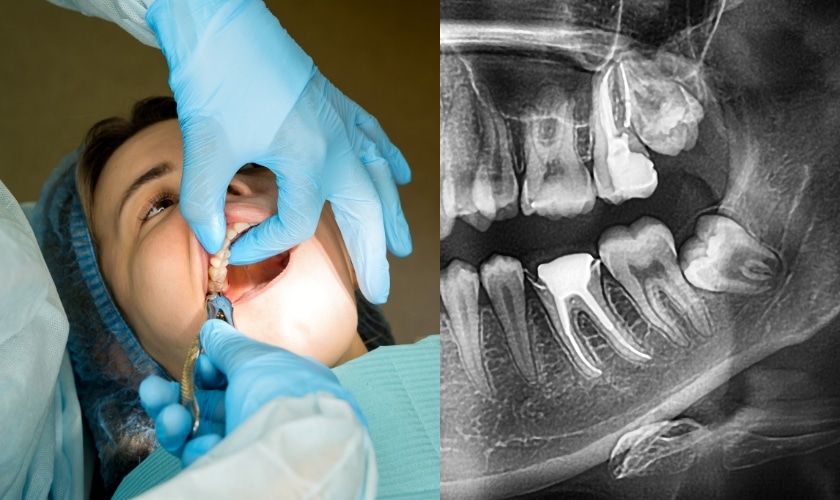

Before the actual wisdom teeth removal process begins, your dentist will conduct a thorough examination and take X-rays to assess the condition of your wisdom teeth. This evaluation helps determine if extraction is necessary.

To ensure your comfort throughout the procedure, you will be given either local anesthesia or sedation on the day of the procedure. The tooth and bone will then be visible through an incision made by the dentist in your gum tissue. To make the tooth extraction process easier, it might occasionally be necessary to remove a tiny amount of the surrounding bone.

Your dentist will use specialized tools to carefully loosen and remove each wisdom tooth once access has been gained. Subsequently, they will remove any leftover debris from the surrounding area and use dissolvable stitches to close the wounds.